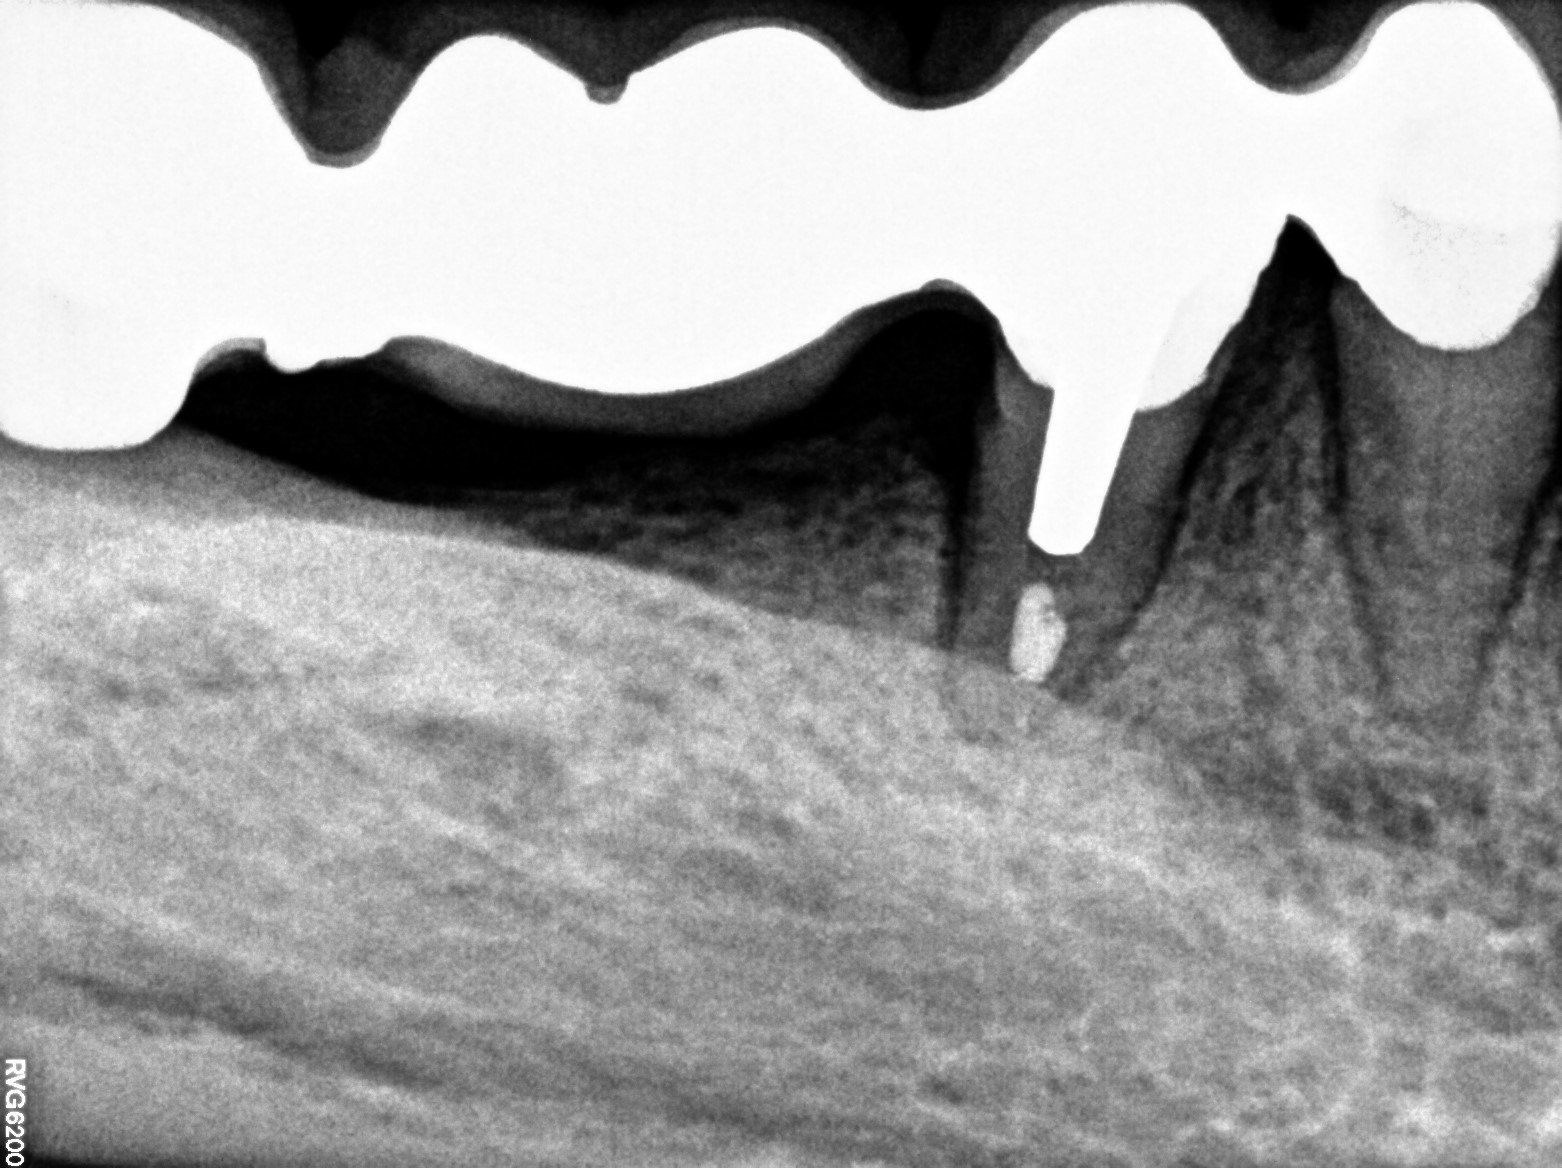

(la terza e quarta radiografia illustrano la devitalizzazione del dente senza l'eliminazione della capsula esistente ma solo con perforazione e ricostruzione nel punto preciso su capsula esistente).